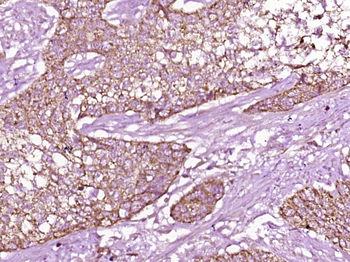

IF, IHC-Fr, IHC-P, WB

应用稀释比例:WB=1:500-2000, IHC-P=1:100-500, IHC-F=1:100-500, IF=1:100-500